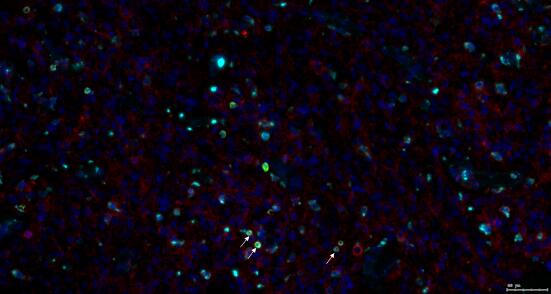

4、组织免疫微环境空间距离分析(细胞社会学)

组织-组织,胞-细胞,细胞-组织的形态/分布/蛋白表达关系的大数据分析

例如:肿瘤区域内的阳性细胞(紫色标记)

距肿瘤区域 25μm 以内的阳性细胞(紫色标记)